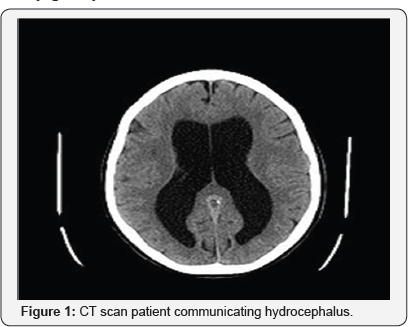

The patient is a single 52 year old woman. With ambiguity regarding her living arrangement and as to how she supports herself. Patient is a very poor historian. On CT scan patient has a communicating hydrocephalus. MRI was seen by neuroradiology and deemed it to be a chronic process possibly due to a remote meningitis or HIV (she is HIV-) and that it is not reflective of her current psychiatric symptoms. She has a steady gait, goes go to the bathroom often, but has no incontinence. In the CPEP she had auditory and visual hallucination, but on the unit she denied them. She was only oriented to self, but could not tell us her age or the year she was born. As per social worker the patient was prescribed Sertraline 50mg in June 2016 by her Psychiatrist. She was also on Citalopram 10 mg in 2014 and Trazodone 50mg in 2014. She has only had one in-patient psychiatry admission in the past 5 years, from 1/1/16-8/4/16.” The patient shows no signs of intoxication or withdrawal to any substance and denies use of any substance abuse in the past.Additionally patient thinks that she has been here for 2 years, while in reality she has been on the unit for only 45 days.

Patient is currently being prescribed Escitalopram PO 20 mg QAM for depressed mood and Methylphenidate 5 mg, PO, BID. According to the neurologist and neuropsychiatrist the patient is so far gone in terms of dementia that she has not been started on any anticholinergic medication as they think that starting the medication now will not do her any good. Patient has been previously treated with trials of anticholinergic medication to no avail (Figure 1).